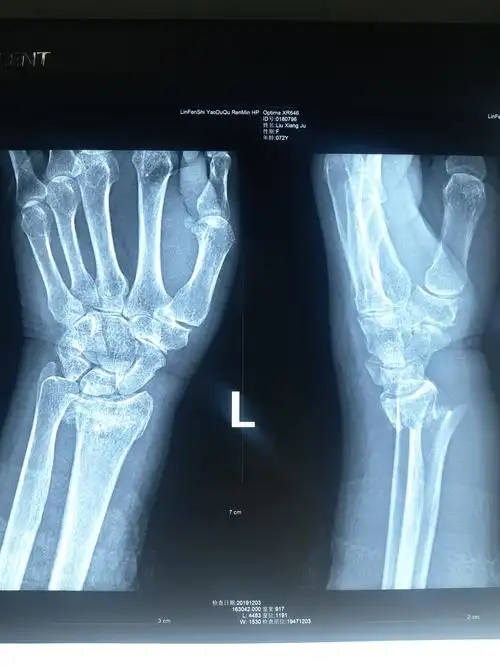

典型的colles骨折

母亲摔伤左腕成colles骨折大家看看复位效果

患者女58岁左colles骨折